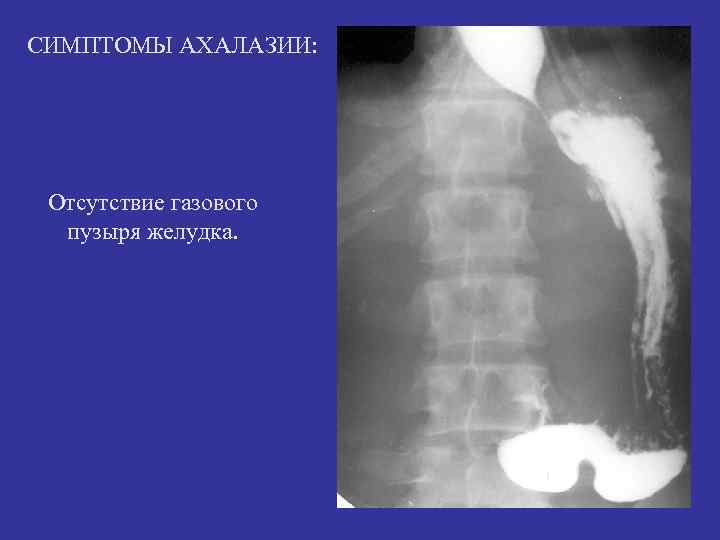

СИМПТОМЫ АХАЛАЗИИ: Р авномерное расширение тени пищевода на всем протяжении и его гипотония.

СИМПТОМЫ АХАЛАЗИИ: Отсутствие газового пузыря желудка.

Диффузное расширение – ахалазия кардии